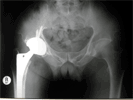

Pre

Op

65 year old male with pain and limping right hip due to osteoarthritis

Post

Total Hip replacement done via minimally invasive single incision